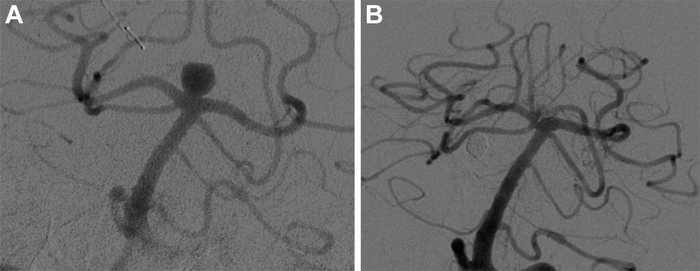

Digital subtraction angiography images show basilar tip aneurysm (A) before and (B) at last follow-up after Woven EndoBridge device placement. Image courtesy of Radiological Society of North America

A braided wire device known as the Woven EndoBridge (WEB) was developed to overcome those limitations. The device is placed inside the aneurysm under angiographic guidance, where it causes a clot to form, closing off the aneurysm and reducing the risk of bleeding without requiring supporting stents or blood thinners.

“After you put the WEB device through the neck of the aneurysm, it opens up,” Adeeb said. “Given that it’s bigger than the neck of the aneurysm, it usually stays in place. One quick procedure is usually enough for successful treatment.”